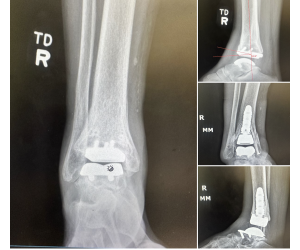

Ankle Fracture with Intercalary Fragments - Update

Maximilian Heitmann

Following up on my previous post that showed the preoperative CT slices. https://lnkd.in/e74BVTPn See also this previous case discussion...